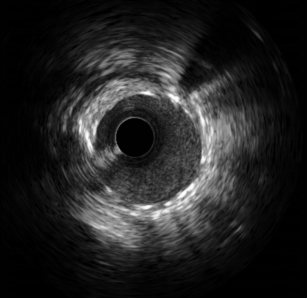

术中,造影结果与术前判断一致,患者前降支血管重度狭窄且病变累及较大分支血管开口,需要介入治疗。公永太教授带领介入团队,凭借精湛的手术技巧,首先分别于前降支及分支送入导丝,在分支预埋球囊保护下,于前降支病变部位置入一枚支架,之后再送入导丝穿支架网眼至分支内,完成球囊后扩张和对吻扩张。操作过程中采用IVUS评估病变、优化支架置入,全程未使用对比剂。整个手术的对比剂用量不足15ml,远远少于一例普通患者单纯造影所用剂量。患者术后复查肌酐无增高,心绞痛症状完全缓解,顺利出院。

IVUS示支架贴壁、膨胀良好